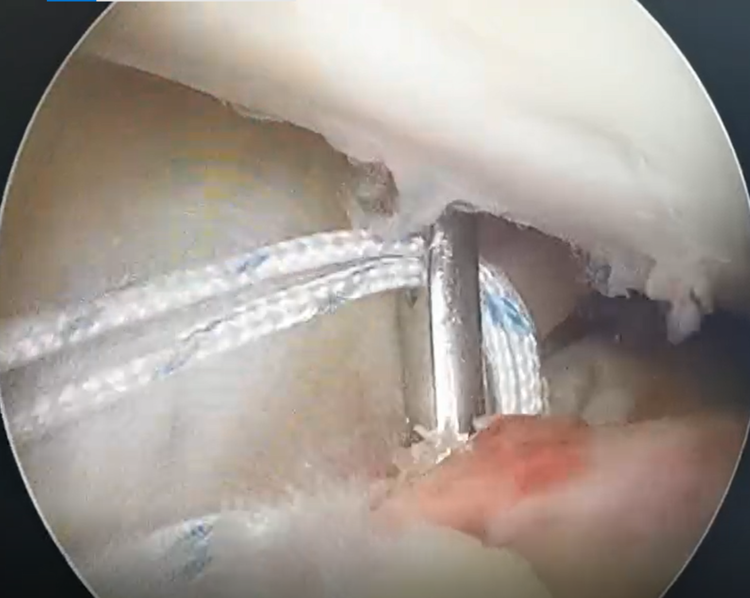

镜下探查见,ACL胫骨止点撕脱骨折,边缘伴少量血痂,内侧胫骨平台骨折,关节面软骨劈裂,无塌陷。

关节镜下,PDS-Ⅱ缝线牵引高强度缝线编织缝合ACL。

三角形缝合固定后,牵拉高强度线见撕脱骨折复位,稳定。

前抽屉状态下,肩关节外排钉于胫骨骨道挤压固定缝线。